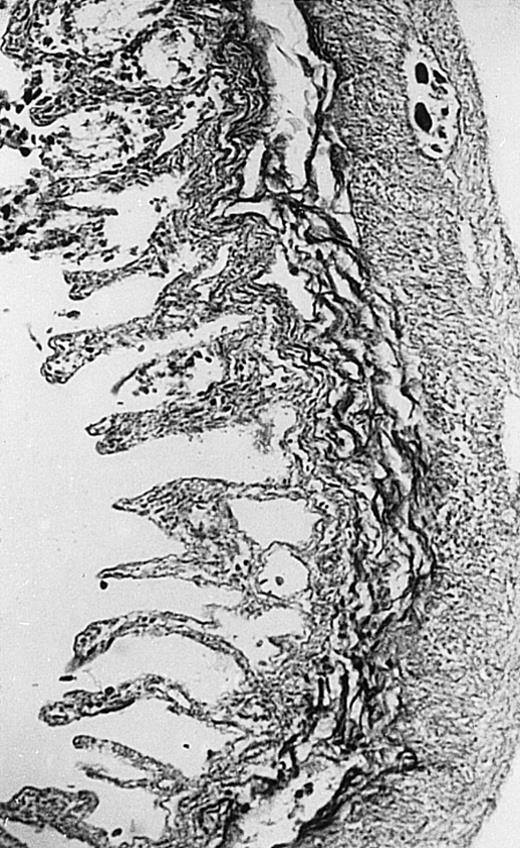

Pathologic findings in the small and large intestine were strikingly different depending on the treatment group. Figure 2A shows a representative pathologic sample from an animal assigned to the control group. Marked thinning of the bowel wall and extensive areas of epithelial cell sloughing was noted. Animals randomized to rhG-CSF treatment had minimal improvement in histologic findings with focal regions of preserved epithelium (Fig2B). Animals randomized to the rhIL-11 group showed substantial improvement with thickening of the epithelial layer and preservation of mucosal cell integrity (Fig 2C). Animals receiving both rhG-CSF and rhIL-11 had the most favorable histologic findings with normal mucosal thickness, minimal inflammatory changes, and preserved tissue architecture (Fig 2D). The composite analysis of the gastrointestinal pathology is provided in Table 1.

Histopathology of small intestinal mucosa cut in transection from an animal in each treatment group (study day 8). The upper panel (row 1) is a low power view (original magnification × 57); the lower panel (row 2) is a high power view (original magnification × 144). Note the diffuse thinning and necrosis of the mucosa with sloughing of intestinal epithelial cells in the control animal (A). There is progressive recovery of the thickness of the mucosa, reduction in inflammatory changes, and improved epithelial architecture with rhG-CSF (B), rhIL-11 (C), and combination therapy with rhG-CSF+IL-11 (D).